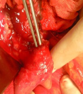

Anatomical forceps within the fistula orifice in the duodenum (Courtesy Dr. V. Penopoulos)